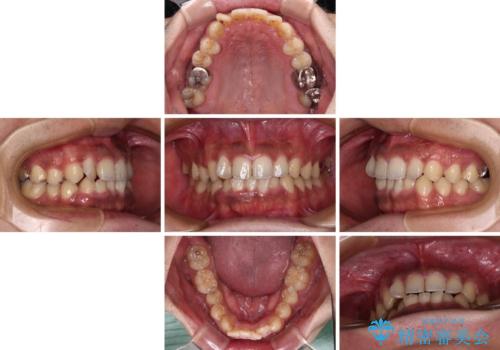

途中2年強の来院がなく、改善されていたデコボコが元に戻ったり、装着時間が不足しており前歯のデコボコは十分に改善することはできませんでしたが、5年間の有効期限内で可能な限り歯列を整えることができました。